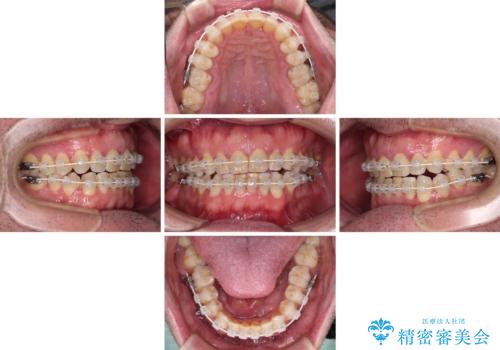

前歯の非接触改善は、インビザラインの得意とするところですが、マウスピース矯正は絶対に継続できないとのことで、ワイヤー装置にて矯正治療を行うこととしました。

舌の突出癖が改善されない限り、非接触改善は見込めないため、トレーニングを徹底するように指示しました。

舌のトレーニング自体は簡単なものですが、無意識下でも舌が突出しないようにしなければならないため、毎日継続することが最大の難関です。